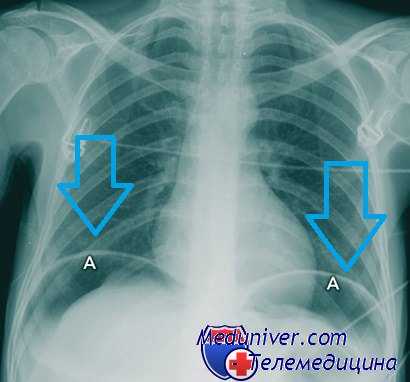

- Рентгенологическое исследование. Рентгенографию с пероральным контрастированием выполняют только после прекращения рвоты и стабилизации состояния. Метод информативен для диагностики органических изменений, грыжевых образований. Затекание контраста за пределы просвета ЖКТ указывает на перфорацию или свищевые ходы.

Из лабораторных методов исследования, помимо общеклинических, применяют реакцию на выявление скрытой крови в кале. Обязательно изучение желудочной секреции. Рентгенологическое исследование позволяет выявить нишу или заподозрить се наличие по ряду косвенных признаков («язвенный желудок», дуоденит, деформация луковицы и др.). Рентгенолог высказывает мнение о характере язвы (каллезная, пенетрирующая, с признаками малигнизации и др.).

Важную роль имеет тщательное изучение анамнеза заболевания, предшествующего кровотечению. Для уточнения диагноза можно прибегнуть к экстренному рентгенологическому исследованию. Однако лучшие результаты даст экстренное эндоскопическое исследование—эзофагогастродуоденоскопия. Эта диагностическая процедура проводится под местным обезболиванием с предварительным промыванием желудка и в большинстве случаев позволяет точно установить диагноз.